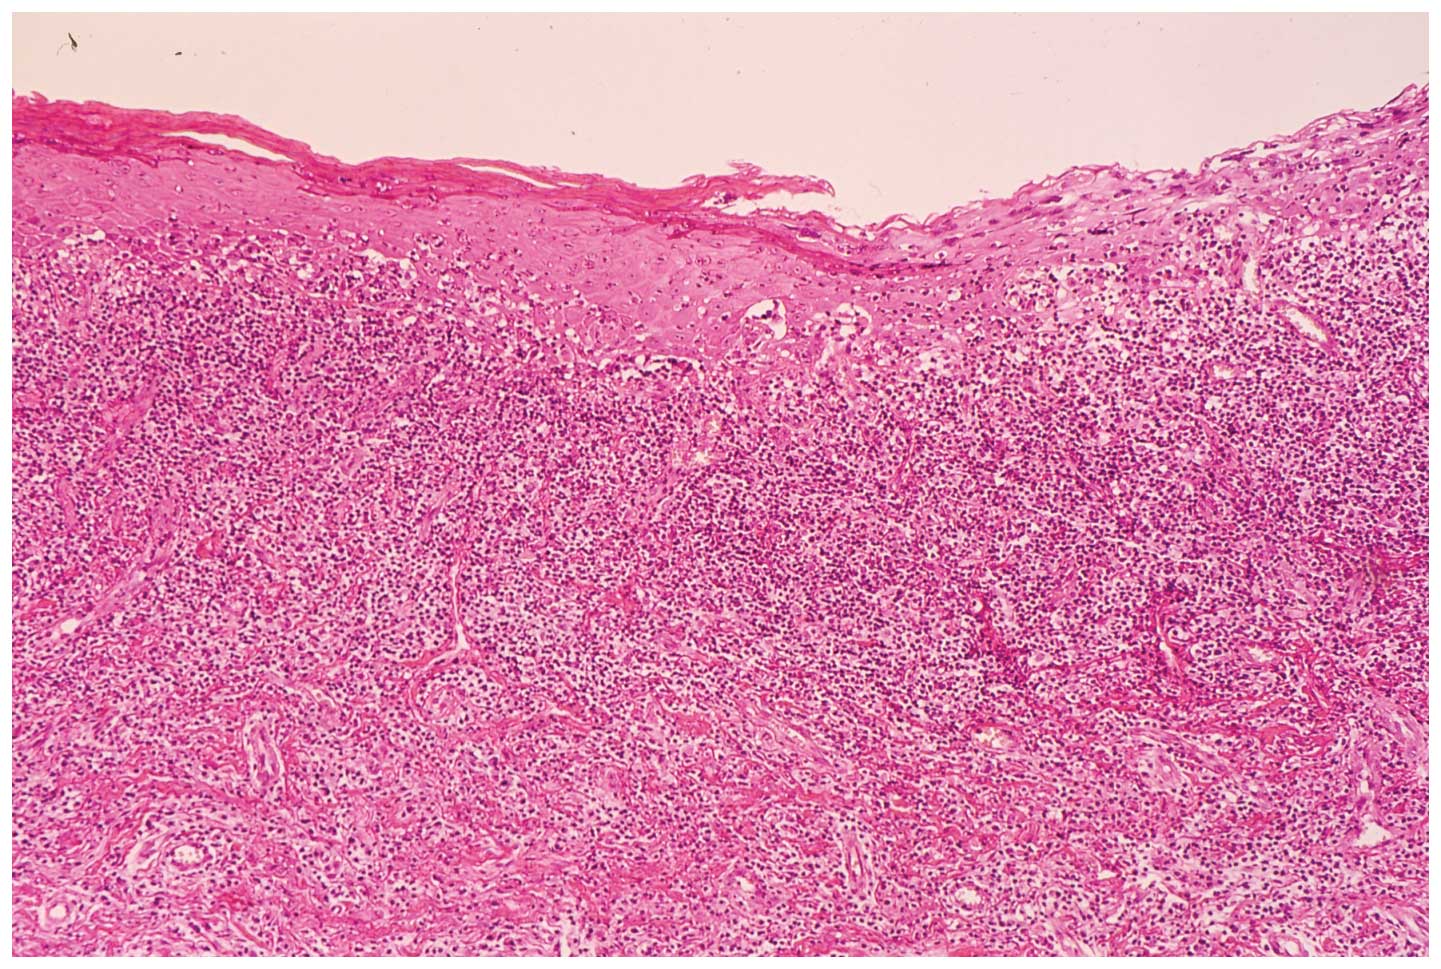

Two biopsy specimens of the buccal mucosa and mandibular alveolar mucosa were characterized by hyperparakeratosis with the thickening of the granular layer, a subepithelial band of infiltration of lymphocytes and liquefied degeneration of the basal cell layer. Histopathological findings were consistent with a diagnosis of OLP (Fig. 2).

Figure 2.

Biopsy specimens from the right buccal mucosa.